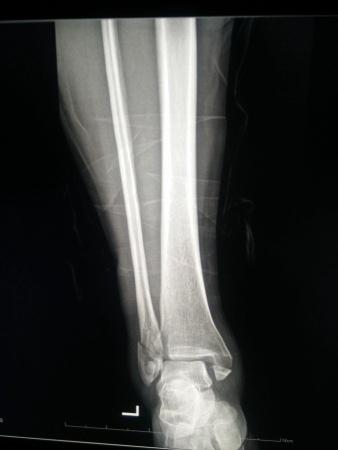

左三踝骨折手术治疗

患者女,外伤后左踝关节活动受限1小时入院,

入院后查体:左踝关节肿胀,活动受限,行DR及左踝关节CT检查,如下图,手术待肿胀消退后行手术治疗,目前愈合良好,请问问各位老师,好久可以下地呀, 下胫腓联合镙钉3个月取呀,

这个下胫腓螺钉真的没有必要打,另外后踝的两枚螺钉怪怪的,从后往前打的,看着钉子帽偏内侧,这个应该在外侧才对,

下胫腓联合单钉固定小心断钉

下胫腓拉力钉一般一个月到一个半月取出!下地需骨折愈合情况而定,下地时需拄拐,患肢尽量不负重行走。